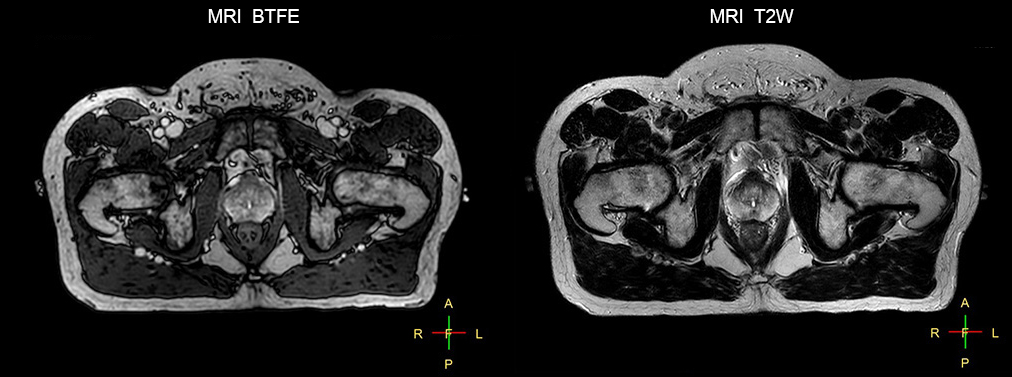

Beaumont Health System (Royal Oak, Michigan, USA) is one of the largest health systems in the USA, with eight hospitals and 153 outpatient sites, a medical school and a research institute. The Radiation Oncology (RO) department houses a dedicated Ingenia MR-RT solution that is routinely used for clinical and research MR-RT activities. “The main reason to integrate MR imaging in RT planning is the superb soft tissue contrast that allows detailed delineation of tumors and healthy organs, which is crucial for RT planning,” says Craig W. Stevens MD, PhD. “MR also provides information on functional and biological activities in tumors, background tissue and normal organs, which may also be used in RT planning,” says physicist Di Yan, DSc, FAAPM.” “We currently use MR-RT mainly in the abdomen and pelvis region: prostate, colorectal, pancreatic, cervical, and liver. Also in the brain, we are starting to use it,” says Dr. Yan.

“The biggest problem for CT-based planning, especially in prostate, is you can’t see the cancer very well,” says Dr. Stevens. “On CT it can be quite challenging to see the edge of the prostate especially at the apex. When the edge of the prostate can’t be delineated well on CT, radiation oncologists will increase their margins a little bit so they don’t miss it, but that can also increase toxicity.” “Using MR, the prostate is well delineated. We quickly see the edges of cancerous tumors like in prostate cancer, and as normal structures can be defined, we can optimize the treatment plan to protect these organs and their normal function. This can potentially improve the outcome. And it improves workflow as well. We can contour more quickly, confident that the tumor is going to be in the field.” “The Ingenia 3.0T MR scanner provides high resolution allowing us to make scans fast for the patients. It also gives the potential to include methods like MR spectroscopy and diffusion weighted Imaging, which we’re in the process of doing right now,” Dr. Stevens adds.

“When a patient registers, first CT simulation and MR simulation are done, followed by CT-MR registration on Pinnacle3. Then the target and normal organ delineation is performed on MR images. Meanwhile we create a reference CT image for online treatment and localization correction. During the treatment phase we can perform additional MRI scans to visualize the anatomy changes and create an adaptive plan. This plan basically adapts the treatment plan to the changes.” “Along with its great benefits, MR has introduced some new challenges,” Dr. Stevens says. “Radiation therapy teams generally have no experience with MR. The Philips training helped us to implement fully the things we can do with the Ingenia MR-RT system. So the training, as well as having a good MR physicist, is critical.”